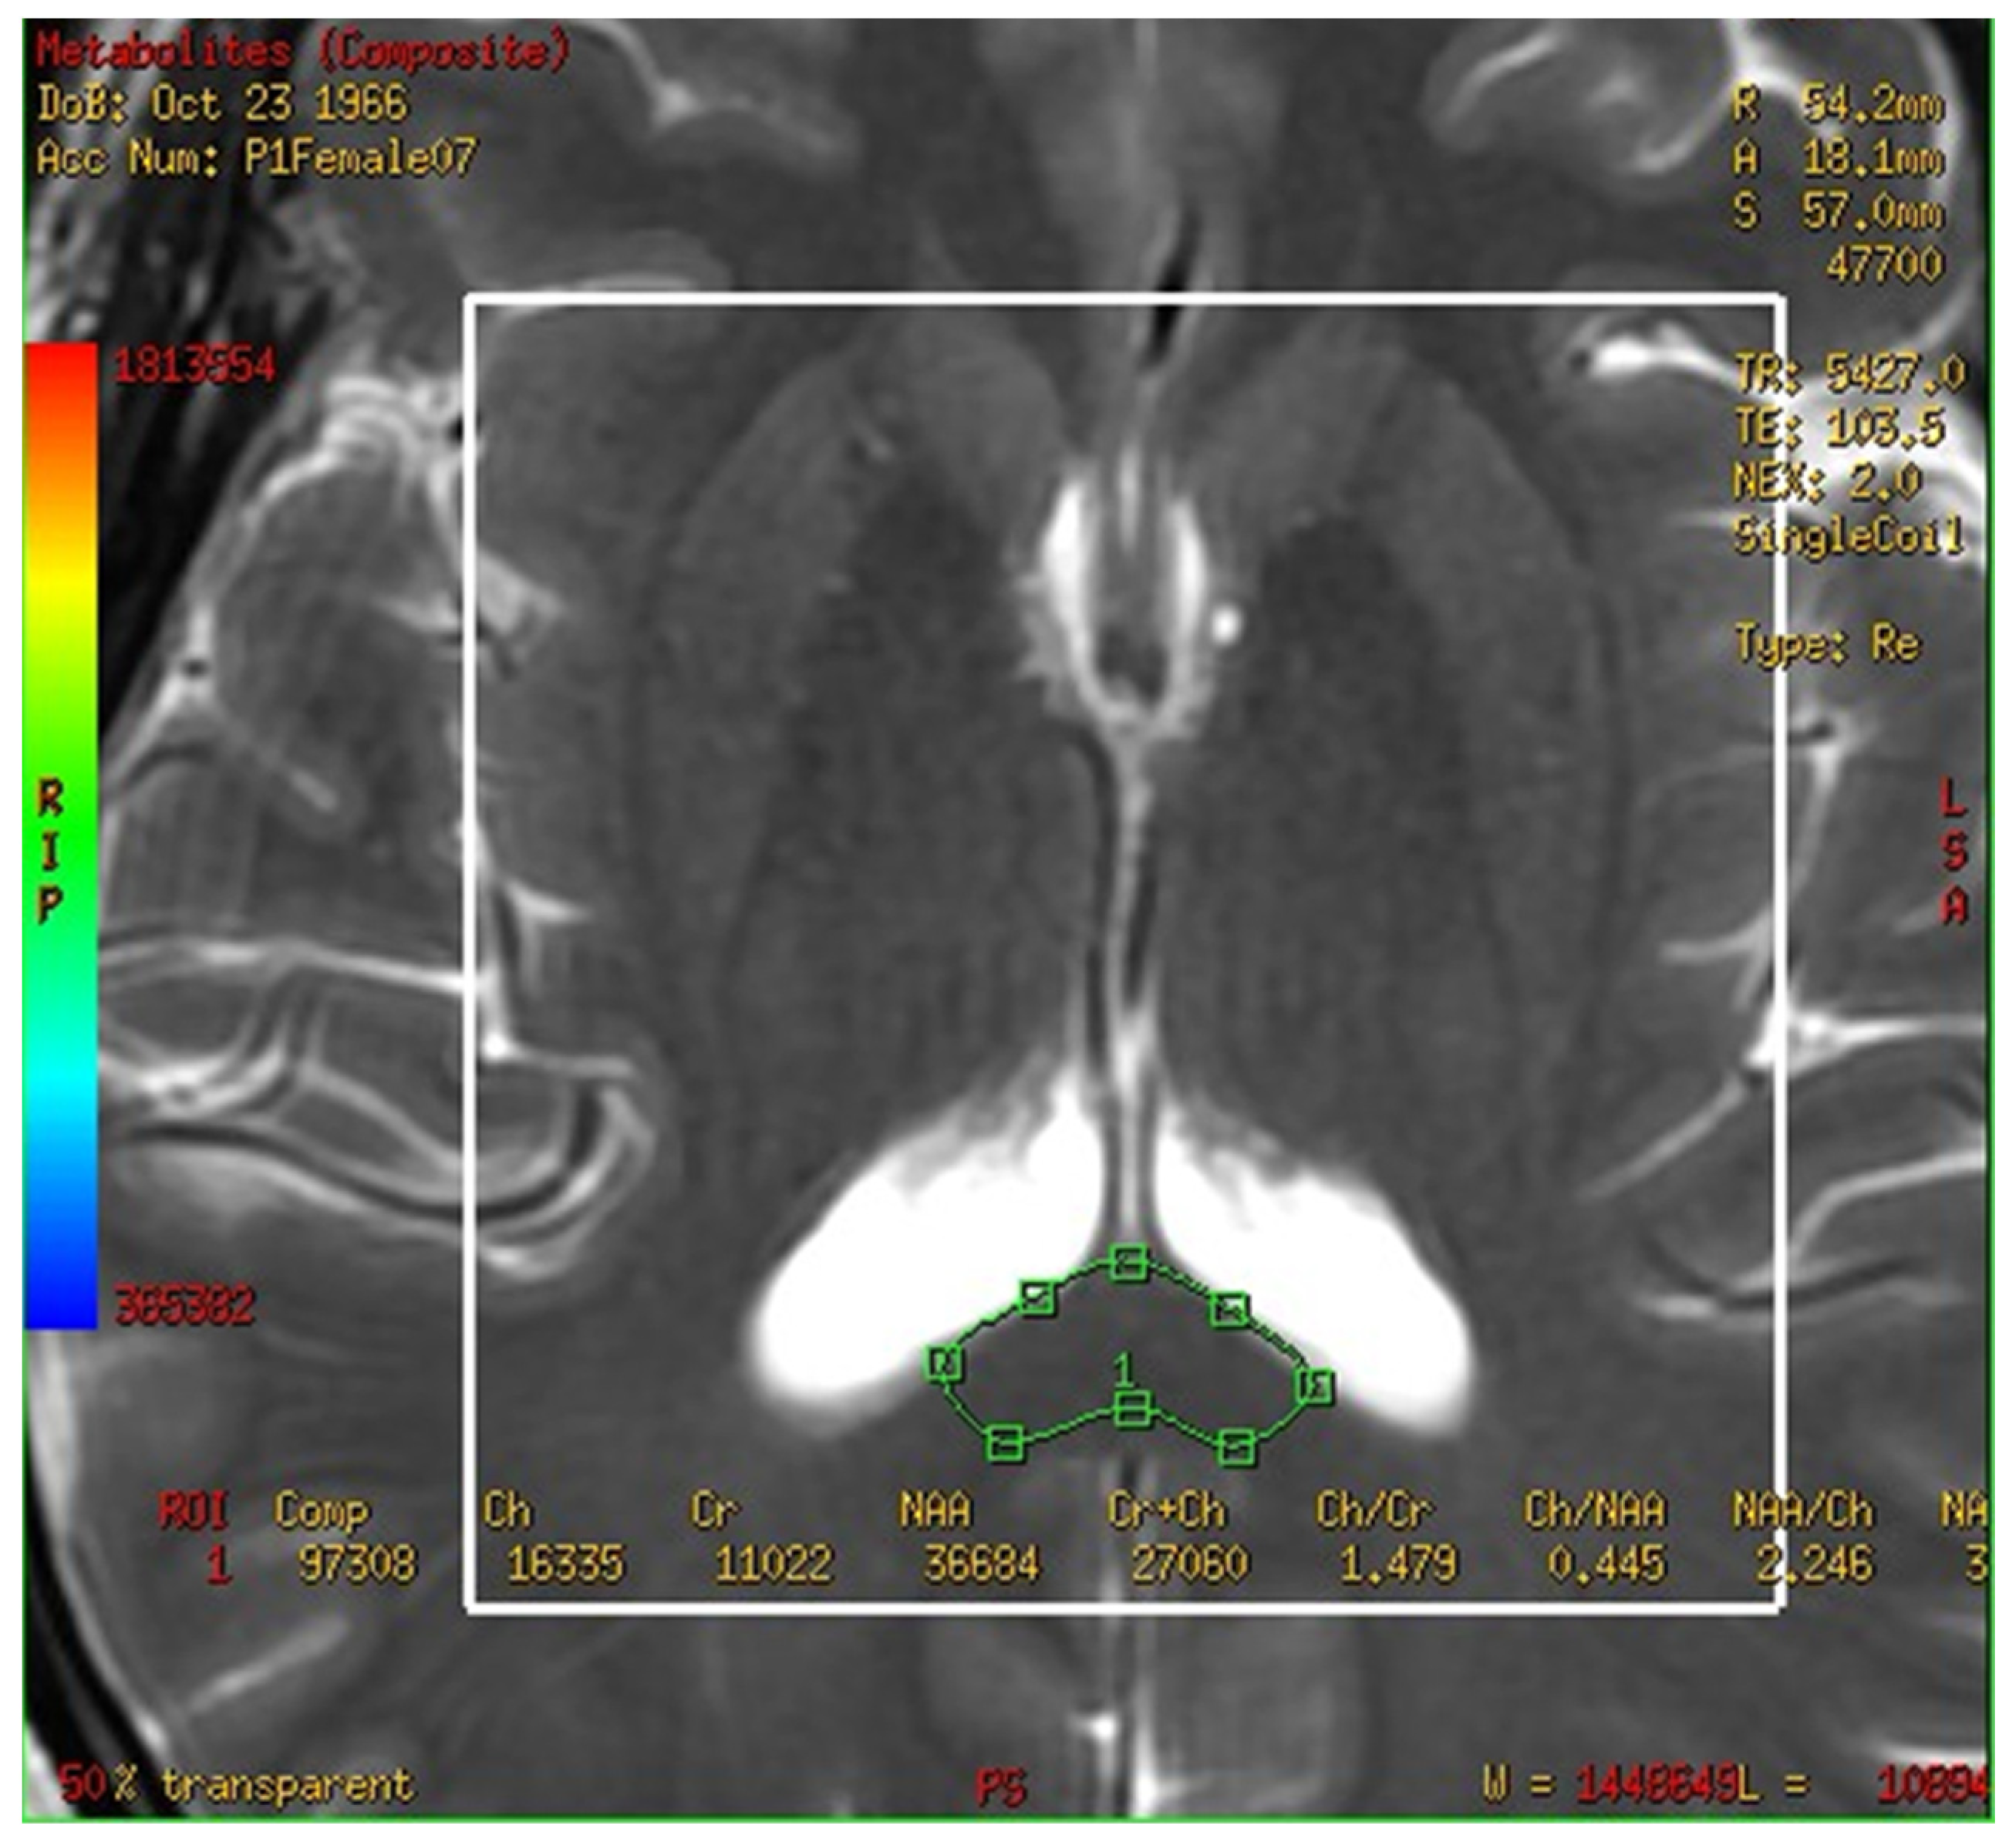

The multivoxel 1H MRS of one subject from 1.5 T MRI is shown in Figure 3A. The fusion map of the 2-D multi-voxel spectrum and image from the same patient was shown in Figure 3B in one section.

Figure 3.

The multivoxel 1H Magnetic resonance spectroscopy with three-dimensional chemical shift images in one subject brain from 1.5 T MRI (A). The fusion map of 2-D multi-voxel spectrum and image from the same patient were analysis (B). Y-axis is the integral of peak.